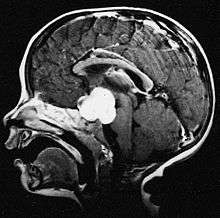

Pilocytic astrocytomas are often cystic, and, if solid, tend to be well-circumscribed. It is characteristically easily seen on CT scans and MRI.

Usually—depending on the interview of the patient and after a clinical exam which includes a neurological exam, and an ophthalmological exam—a CT scan and or MRI scan will be performed. A special dye may be injected into a vein before these scans to provide contrast and make tumors easier to identify. The neoplasm will be clearly visible.

Macroscopically, an astrocytoma is a mass that looks well-circumscribed and has a large cyst. The neoplasm may also be solid.

Under the microscope, the tumor is seen to be composed of bipolar cells with long "hairlike" GFAP-positive processes, giving the designation "pilocytic" (that is, made up of cells that look like fibers when viewed under a microscope[8]). Some pilocytic astrocytomas may be more fibrillary and dense in composition. There is often presence of Rosenthal fibers,[9] eosinophilic granular bodies and microcysts. Myxoid foci and oligodendroglioma-like cells may also be present, though non-specific. Long-standing lesions may show hemosiderin-laden macrophages and calcifications.